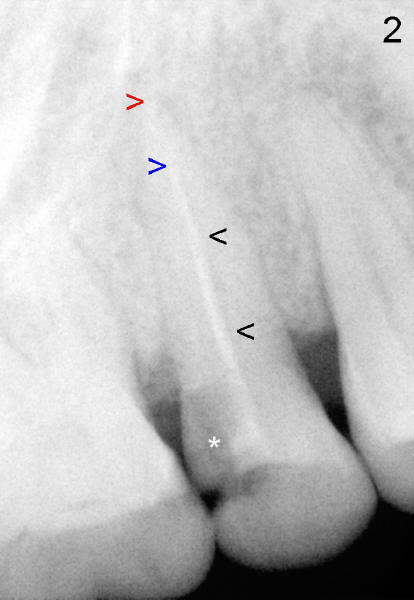

A 50-year-old oriental lady comes to our clinic with chief complaint "I have toothache after filling comes out. Can you just place a filling back?". She had RCT done in her home country. Exam shows that the upper right 2nd premolar (#4) has DO caries (* in Fig.1 (mirror view after placement of rubber dam) ) and occlusal composite (arrowheads). This tooth has severe percussion and moderate mobility. X-ray confirms the DO carious lesion (Fig.2 *). It appears that root canal filling is short (between red and blue arrowheads) and that the filling is not solid. There is a space lateral to the filling (black arrowheads). It seems logical to redo the RCT by removing the old RC filling, extending debridement to the apex and condensing the space better. On re-opening the access, the situation is quite different. Can you guess what it is?